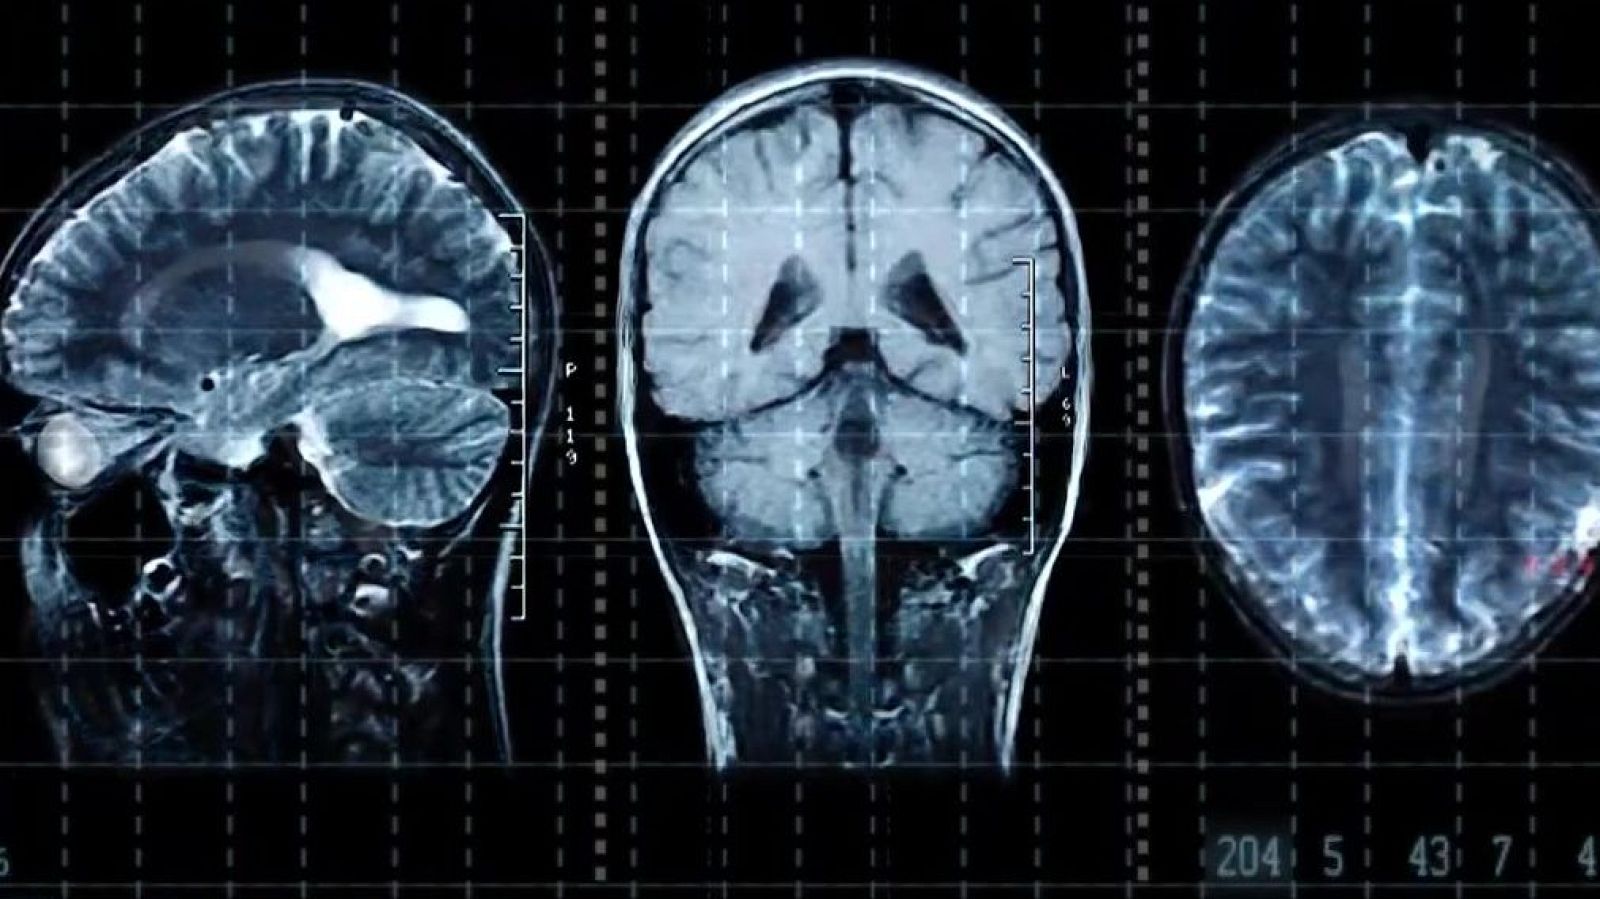

El divulgador científic Luis Quevedo explica a 'L'Altaveu' un estudi de la Universitat d'Oxford que ha detectat les cinc edats crucials del cervell.

Un estudi de la Universitat d'Oxford diu que als 9, 32, 66 i 83 anys es produeixen els canvis cerebrals vitals: el descobriment ajudaria a crear tractaments preventius o terapèutics per combatre l'envelliment neuronal. El divulgador científic Luis Quevedo interpreta a L'Altaveu les conclusions d'aquest estudi.